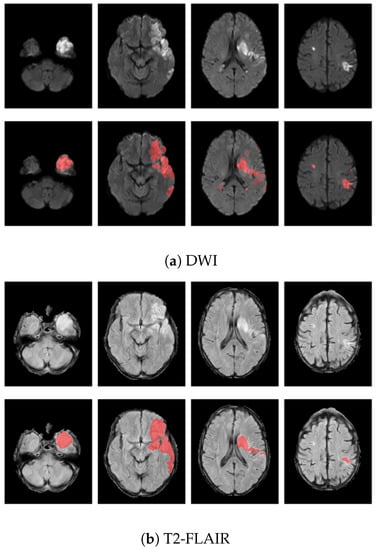

Infarcts in DWI scans were automatically segmented using a deep learning software developed in-house and then manually checked and corrected by two expert neuroradiologists (with more than twenty and five years of experience, respectively) using ITK-SNAP software [22]. Infarcts in T2-FLAIR sequences were automatically segmented using DeepNeuroSeg [23], a deep fully convolutional network trained to detect white matter hyperintensities (WMH) from FLAIR that ranked first in WMH Segmentation Challenge at MICCAI 2017. All resulting segmentations were manually checked and corrected using ITK-SNAP software. Figure 4 shows an example of T2-FLAIR and DWI lesion segmentation from the same patient. For each modality, a few slices sampled from the preprocessed scan are reported in the first line. Lesions appear hyperintense on both imaging modalities, and the segmented area after the preprocessing steps (red) is displayed as overlapping the original slices in the second row.

Figure 4. Example of infarct lesion segmentation on a selected slices sampled from (a) DWI and (b) T2-FLAIR preprocessed volumes. For each modality, original slices are displayed in the first row and lesion segmentation (red) is shown as overlapping the correspondent slices in the second row.